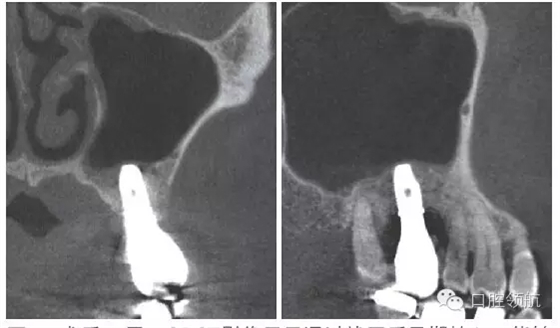

因為垂直骨量少,在植入種植體后,為防止種植體進入上頜竇內(nèi),選擇了安裝直徑大的覆蓋螺絲(圖5、圖6)。 術后CBCT證實上頜竇底提升了足夠的骨量(圖7)。

圖5 植入種植體后,為防止種植體進入上頜竇內(nèi),選擇安裝直徑大的覆蓋螺絲。

圖7 術后CBCT證實上頜竇底充分提升。

術后12周在獲得骨結(jié)合后,開始制作上部結(jié)構(gòu),術后16周戴入(圖8)。術后24周,CBCT影像顯示,種植體周圍有足夠的骨量(圖9)。

圖9 術后24周,CBCT影像顯示通過拔牙后早期植入,能夠進行安全確實的上頜竇底提升術。